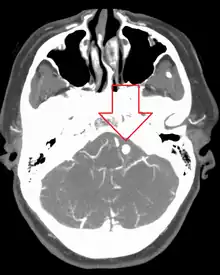

| Angiography of an aneurysm in a brain artery. The aneurysm is the large bulge in the center of the image. | |

Diagnosis of a ruptured cerebral aneurysm is commonly made by finding signs of subarachnoid hemorrhage on a computed tomography (CT) scan. If the CT scan is negative but a ruptured aneurysm is still suspected based on clinical findings, a lumbar puncture can be performed to detect blood in the cerebrospinal fluid. Computed tomography angiography (CTA) is an alternative to traditional angiography and can be performed without the need for arterial catheterization. This test combines a regular CT scan with a contrast dye injected into a vein. Once the dye is injected into a vein, it travels to the cerebral arteries, and images are created using a CT scan. These images show exactly how blood flows into the brain arteries.

Cerebral aneurysms, also known as intracranial or brain aneurysms, occur most commonly in the anterior cerebral artery, which is part of the circle of Willis. This can cause severe strokes leading to death. The next most common sites of cerebral aneurysm occurrence are in the internal carotid artery.[34]